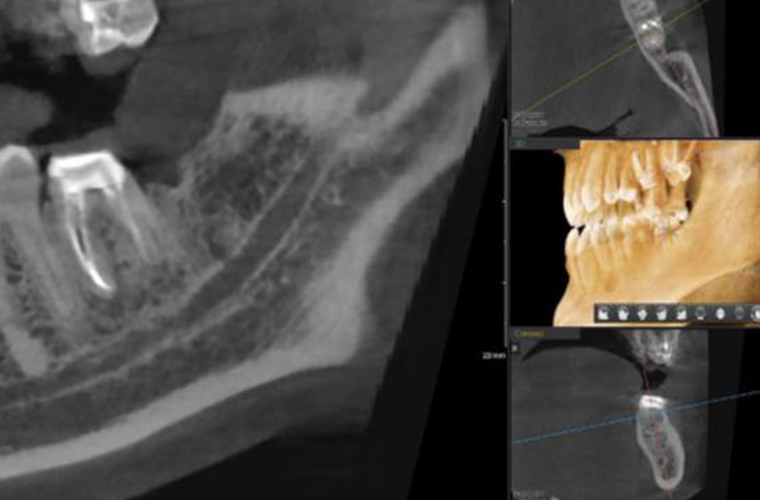

Выявляется преимущественно на рентгене или KЛKT.

По донным КЛКТ отмечается положительная динамика — очаг деструкции костной ткани значительно уменьшился.